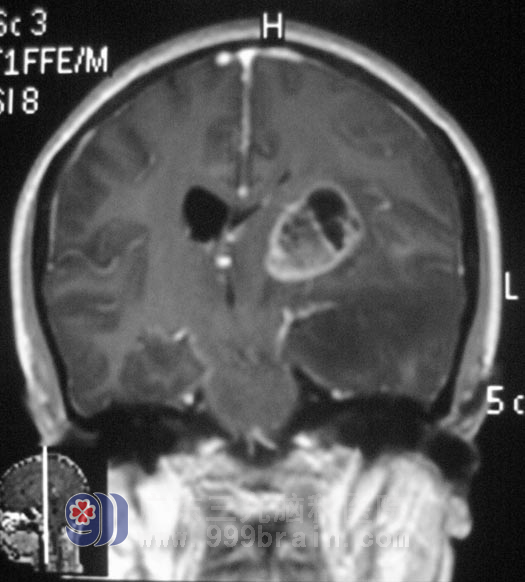

唐女士今年42岁,近半个月时间经常感觉头痛。以为是神经衰弱,脑供血不足,颈椎有问题,服用安神补脑液、颈复康等药物,没有做过检查。两天前无明显诱因出现头痛伴右侧肢体麻木,当地医院CT检查提示“左侧基底节区占位,考虑恶性肿瘤”。在广州某大医院头颅MR证实为:左侧基底节区占位,考虑恶性肿瘤。http://www.999brain.com/

广东三九脑科医院综合神经外科 鲁明主任结合唐女士的病史和影像资料,初步判断为星形细胞瘤:

7月27日,由鲁明主任主刀,在全麻下行左侧基底节区肿瘤切除+左侧颞叶部分切除内减压术,使用导航仪定位,切开后见肿瘤呈灰白色烂鱼肉样,边界不清,在显微镜下切除基底节区外侧及前侧肿瘤,后侧肿瘤部分切除,左侧颞叶颞极脑组织水肿厉害,予部分颞叶切除,缓解颅内压力。手术过程顺利。术后予专科监护,唐女士顺利度过水肿期和出血期,感觉和肢体活动功能无异常,视物正常。病理证实为: 间变性星形细胞瘤 III级。入放疗科进一步治疗。